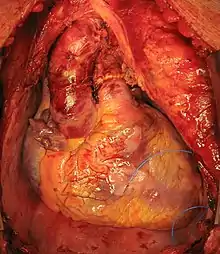

Trasplante ortotópico

El trasplante cardíaco ortotópico comienza cuando el cirujano realiza una incisión a lo largo del esternón para dejar expuesto el mediastino. El pericardio se abre, las grandes válvulas son diseccionadas y al paciente se le realiza un baipás cardiovascular. El corazón enfermo se retira mediante el corte transversal de las válvulas y una parte de la aurícula cardiaca. La vena pulmonar no es seccionada; se deja una buena porción circular del atrio para que contenga la vena pulmonar a la derecha del emplazamiento. El corazón del donante es cuidadosamente ajustado en el restante espacio de la aurícula y válvulas y suturar la zona. El nuevo corazón es reiniciado, el paciente es desconectado del baipás cardiopulmonar.